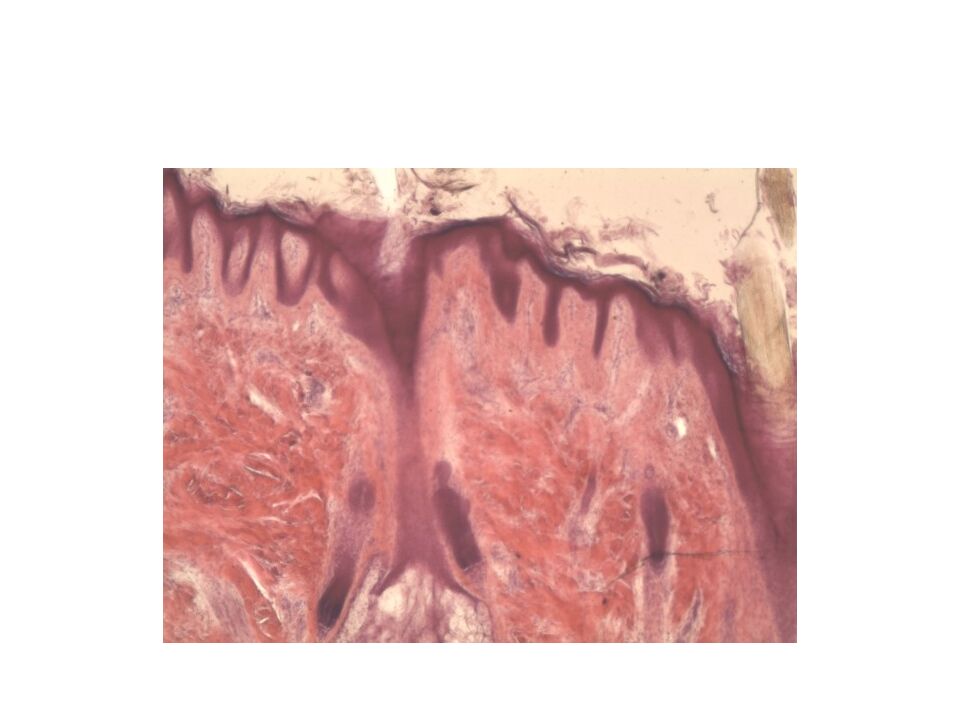

Слайд 7: Кожа пальца

А. Эпидермис 1. базальный слой 2. шиповатый слой 3. зернистый слой 4. блестящий слой 5. роговой слой Б. Дерма 6. сосочковый слой 7. сетчатый слой 8. кровеносный сосуд В. Гиподерма Г. Потовая железа: а. концевой отдел б. выводной проток А 1 2 3 4 5 8 7 Б В 6 а б Г